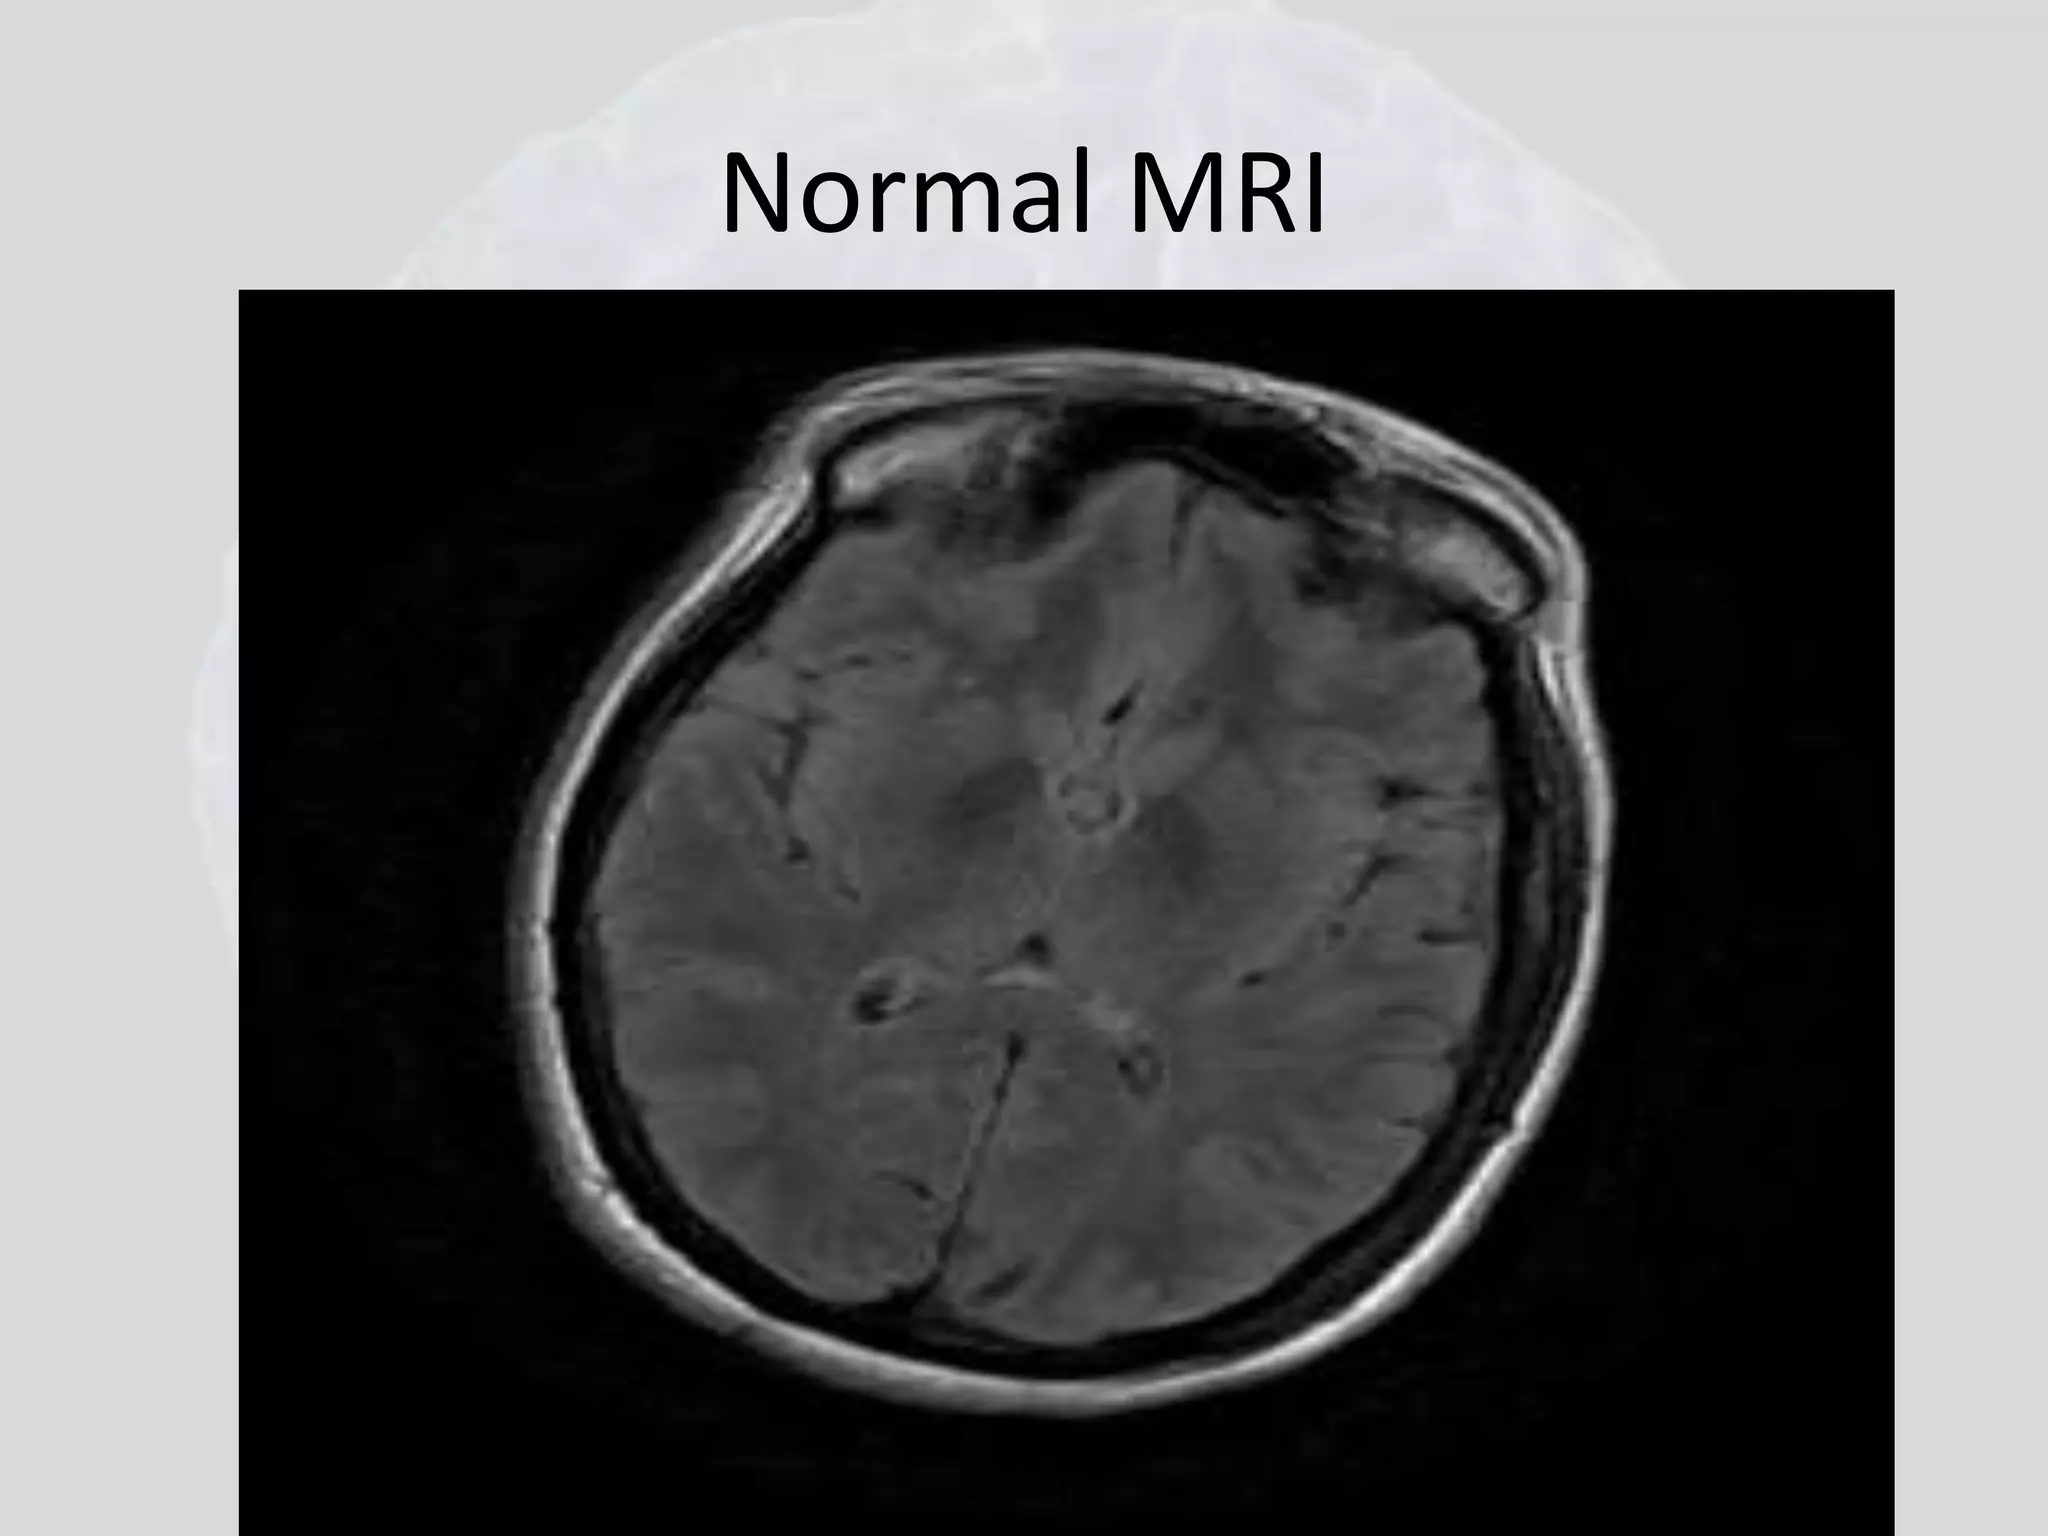

Normal MRI

MRI T1 T2 axial sections showing normal anatomy. (A) T,-weighted section shows CSF black and clear differentiation between white and grey matter. (B-G) T2-weighted sections in another patient show CSF white and white matter dark while grey matter remains grey.